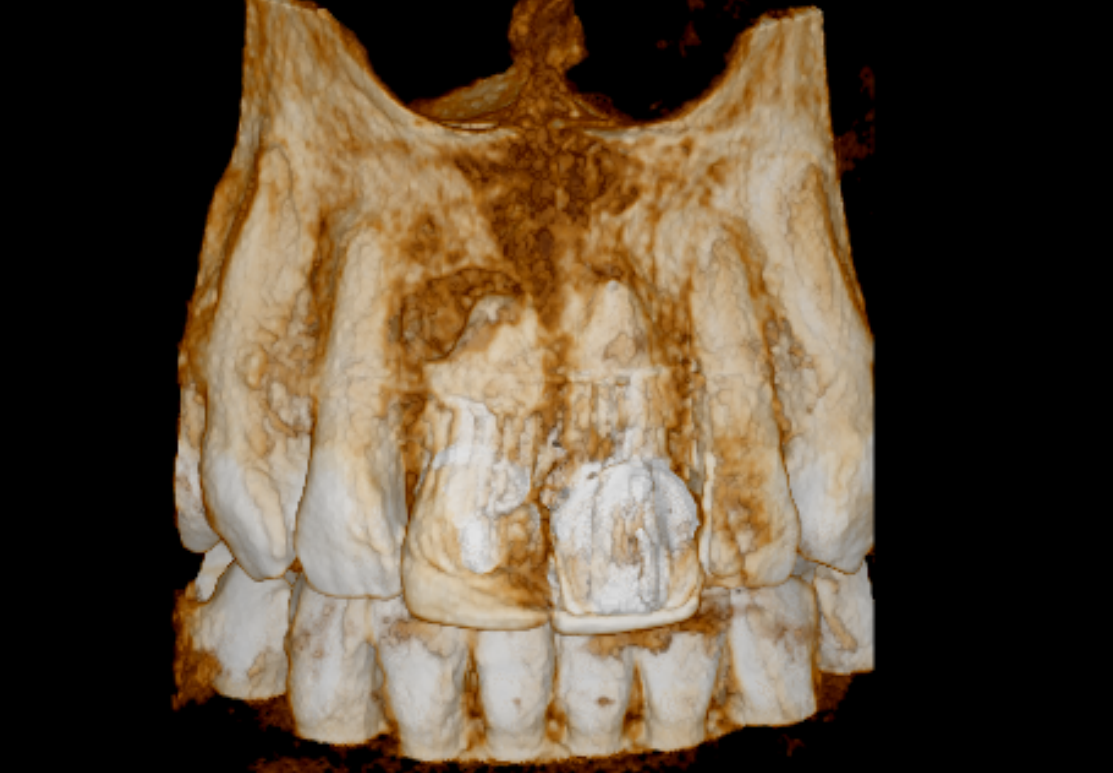

Case 26 – Endodontics

Repeat apicectomy with grafting